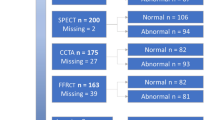

Myocardial ischemia detection has played a pivotal role in the identification of symptomatic intermediate risk patients who could receive benefit from invasive evaluation [1–4]. Myocardial ischemia can manifest with symptoms of shortness of breath or chest pain and even myocardial infarction and cardiac death. Although the role of coronary revascularization in acute ST and non-ST-segment elevation myocardial infarction is crucial for beneficial outcomes, in patients with stable CAD, the widespread use of revascularization is debated [5–7]. Therefore, the choice between a conservative or invasive approach in stable CAD is oftentimes challenging and mainly based on the severity of the hemodynamic effects associated with atherosclerotic lesions. To this regard, the combination of an anatomical evaluation of CAD with ICA bridged with the functional relevance of specific coronary artery lesions by invasive fractional flow reserve (FFR) is now considered the gold standard test in therapeutic decision making. FFR, the ratio of maximal hyperemic blood flow of a stenosis divided by normal hyperemic blood flow in the absence of stenosis, determines the functional significance of CAD in a lesion-specific manner. FFR-guided revascularization has been shown to improve outcomes and reduce health care costs [8••, 9••]. Although, both ICA and FFR provide combined anatomical and functional information regarding the severity of CAD, they are invasive and expensive techniques employing the use of ionizing radiation. With this understanding, there are several non-invasive modalities used in clinical practice for the functional assessment of CAD including exercise-ECG, stress echocardiography (Echo) [10], single-photon emission computed tomography (SPECT), or advanced non-invasive techniques such as stress cardiac magnetic resonance (CMR) and positron emission tomography (PET) [11]. However, recent literature has reported the low diagnostic yield of obstructive CAD at the time of ICA after undergoing standard-of-care non-invasive functional stress testing [12••, 13].

In the EVINCI trial, Neglia et al. [16••] showed that CCTA is more accurate as compared to functional imaging in patients with suspected CAD. However, whether the superior diagnostic performance translates into improved outcomes is still issue of concern. Large registries note that early detection of sub-clinical CAD is correlated with worst outcomes [17••, 18]. Recently, data from the SCOT-HEART trial concluded that a CCTA diagnostic strategy alters therapeutic interventions which translated into reduced hard clinical endpoints such as myocardial infarction [19••]. On the other side, Douglas et al. [20••] showed that CCTA, as compared to a functional stress testing strategy was associated with a lower rate of non-obstructive CAD at ICA evaluation (3.4 vs. 4.3 %, p = 0.02) with a trend of higher number of patients referred to catheterization (12.2 vs. 8.0 %) and revascularization procedures (6.2 vs. 3.2 %) with equivalent clinical outcomes. For this reason, an urgent need for non-invasive techniques that evaluate both the functional and morphological severity of CAD is growing. CCTA has emerged as unique modality providing coronary artery anatomy and, more recently, due to the introduction of stress myocardial computed tomography perfusion (stress-CTP) and non-invasive fractional flow reserve (FFRCT), functional relevance of CAD in a single scan. The current review evaluates the technical aspects and clinical experience of FFRCT and stress-CTP in the evaluation of functionally relevant CAD discussing the strength and weakness of each approach.

The diagnostic accuracy of stress-CTP has been studied by using several reference techniques such as SPECT, invasive FFR, ICA and stress CMR.

In a large cohort of patients from the CORE320 study, a combined approach of CCTA plus static single-energy stress-CTP reported high diagnostic accuracy with an AUC of 0.87 in the identification of flow limiting disease defined as a ≥50 % coronary stenosis by ICA causing a perfusion defect by SPECT [42••].. Similarly, Osawa et al., evaluated the performance of static single-energy stress-CTP compared to CCTA alone and demonstrated a significantly higher AUC of 0.89 versus 0.84 for the detection of CADThe negative predictive value of CCTA alone versus stress CTP increased from 63 to 96 %, respectively [43]. Several other studies have noted the high diagnostic accuracy of static single energy stress-CTP to detect functionally significant CAD [44–46].

There is less data evaluating the diagnostic performance of static dual energy stress-CTP [47–53]. Ko et al. showed improved diagnostic accuracy with CCTA + stress CTP compared to CCTA alone with an AUC of 0.89 versus 0.79, respectively [49].. Furthermore, in high-risk patients, the combined approach of CCTA and stress-CTP acquired in dual energy mode reported diagnostic performance which was superior to SPECT [50]. With the added value of providing quantitative perfusion from dynamic stress-CTP, a MBF cut-off value of 75 ml/100 ml/min has been reported to identify hemodynamically significant CAD [54, 55].. Quantitative MBF on stress-CTPreported a diagnostic accuracy of 82 % when compared to invasive FFR for the detection of hemodynamically significant stenosis [56].

Cardiac CT provides us with a unique non-invasive imaging modality offering fast diagnostic testing that is cost efficient and accurate at providing both anatomic and functional information. Although both FFRCT and stress-CTP represent two excellent techniques for non-invasive assessment of myocardial ischemia, it is important to consider their differences includingprognostic value, radiation dose, and cost-effectiveness. Ongoing studies such as DECIDE gold (ClinicalTrials.gov identifier NCT02178904) will analyze the diagnostic accuracy of dual energy stress-CTP as compared to FFR [60], while in CREDENCE trial (ClinicalTrials.gov identifier NCT02173275) a comparison of FFRCT versus other perfusion imaging modalities such as SPECT and stress-CMR will be studied. Finally, in the PERFECTION study, an intra-patient head to head comparison of per-vessel diagnostic accuracy of FFRCT versus stress-CTP will be performed [61••].